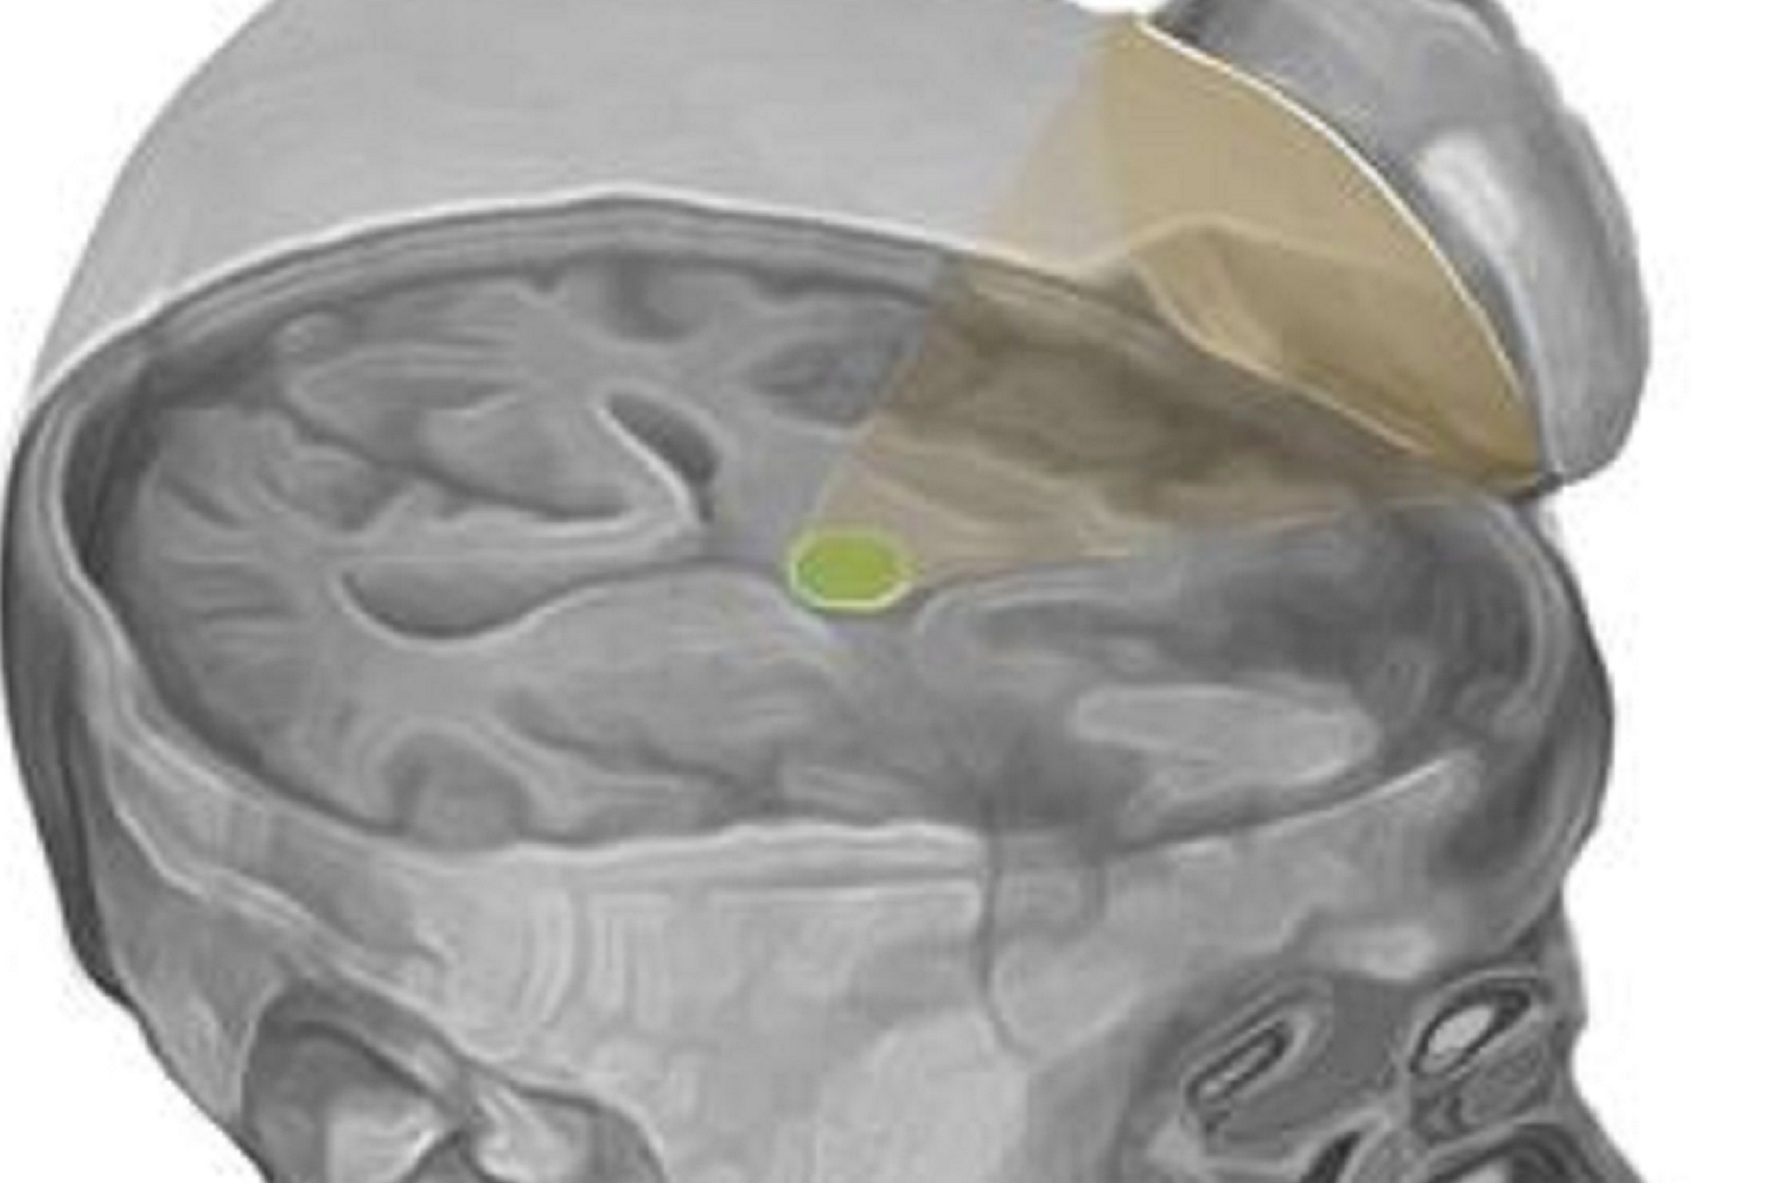

Ilustración de los ultrasonidos dirigidos hacia el tálamo (en verde). Imagen: Martin Monti. Fuente: UCLA.

La técnica utiliza más concretamente la estimulación sónica para excitar las neuronas del tálamo, una estructura que sirve como eje central del cerebro para el procesamiento de la información.

El dispositivo, del tamaño de un platillo de taza de café, genera una pequeña esfera de energía acústica que puede ser dirigida a diferentes regiones del cerebro para excitar el tejido cerebral.

La técnica utiliza más concretamente la estimulación sónica para excitar las neuronas del tálamo, una estructura que sirve como eje central del cerebro para el procesamiento de la información.

El dispositivo, del tamaño de un platillo de taza de café, genera una pequeña esfera de energía acústica que puede ser dirigida a diferentes regiones del cerebro para excitar el tejido cerebral.

Esta técnica se dirige al tálamo porque, en personas cuya función mental está profundamente alterada después de una coma, el rendimiento de esta región cerebral está típicamente disminuido. Normalmente, los medicamentos que se prescriben en estos casos se dirigen al tálamo de manera indirecta.

Esta técnica se dirige al tálamo porque, en personas cuya función mental está profundamente alterada después de una coma, el rendimiento de esta región cerebral está típicamente disminuido. Normalmente, los medicamentos que se prescriben en estos casos se dirigen al tálamo de manera indirecta.